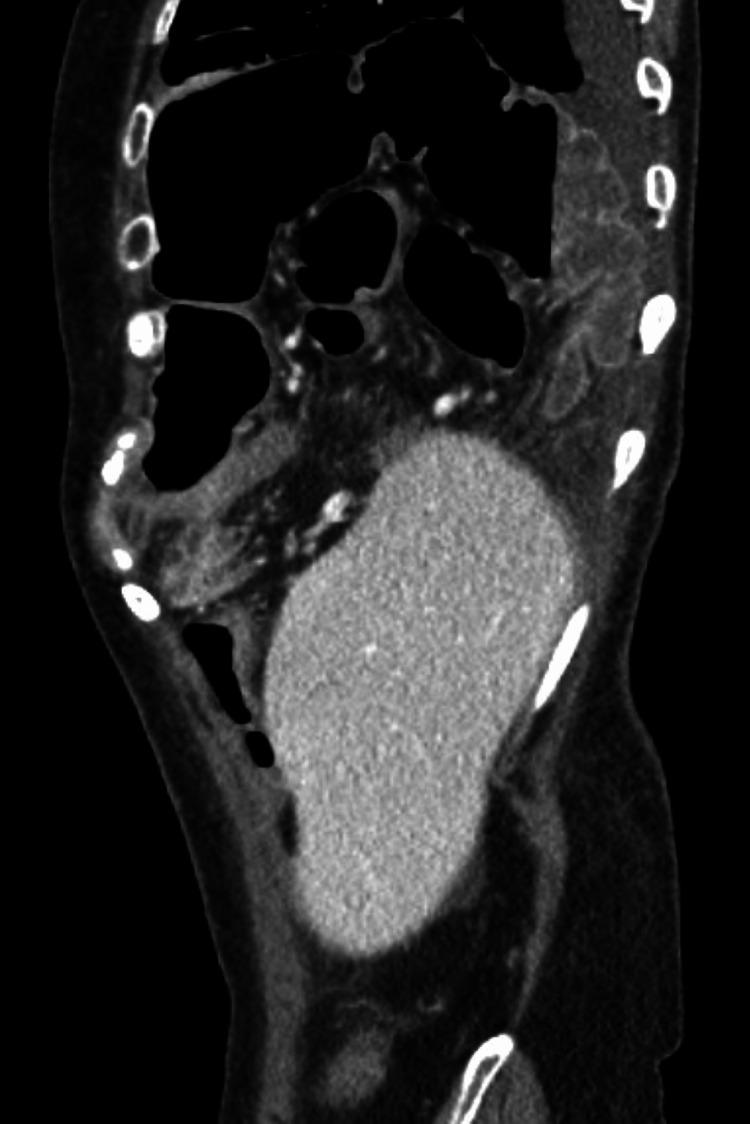

Congenital diaphragmatic hernias (CDH) occur as a result of genetic and environmental factors that occur during the early stages of fetal development. Overall, CDH are considered to be quite rare and are often discovered when patients are neonates. The patient in this case underwent a routine colonoscopy for high-risk polyps but then developed the sudden onset of cramping abdominal pain and PO (per os) intolerance. She was found to have a right-sided diaphragmatic hernia which ultimately required operative intervention. Retrospectively, a close review of prior imaging revealed a potential diaphragm defect. Post-colonoscopy diaphragmatic hernias are very rare and right-sided ones are rarer, making this case report an important addition to the literature.

先天性膈疝(CDH)是由胎儿发育早期的遗传和环境因素导致的。总体而言,CDH被认为相当罕见,通常在患者为新生儿时被发现。该病例中的患者因高危息肉接受了常规结肠镜检查,但随后突然出现腹部绞痛和经口不耐受。她被发现患有右侧膈疝,最终需要手术干预。回顾性地看,对之前的影像学检查进行仔细复查发现了潜在的膈肌缺损。结肠镜检查后发生的膈疝非常罕见,而右侧膈疝则更为罕见,因此本病例报告为文献增添了重要内容。